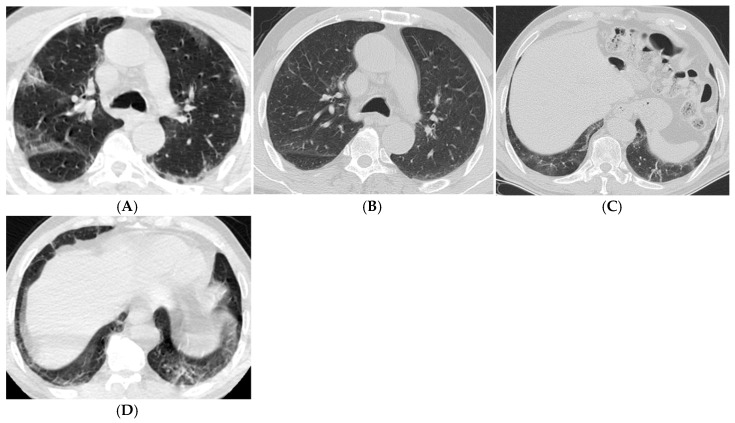

Background: This study aims to systematically evaluate the findings from computed tomography (CT) examinations conducted at least three months post-diagnosis of COVID-19 in patients diagnosed between 2020 and 2024. Objective: To determine the frequency and characteristics of CT findings in the post-COVID-19 period, analyze long-term effects on lung parenchyma, and contribute to the development of clinical follow-up and treatment strategies based on the collected data. Materials and Methods: Ethical approval was obtained for this retrospective study, and individual consent was waived. A total of 76 patients were included in the study, aged 18 and older, diagnosed with COVID-19 between March 2020 and November 2024, who underwent follow-up chest CT scans at 3-6 months, 6-12 months, and/or 12 months post-diagnosis. CT images were obtained in the supine position without contrast and evaluated by two experienced radiologists using a CT severity score (CT-SS) system, which quantifies lung involvement. Statistical analyses were performed using IBM SPSS 23.0, with significance set at p < 0.05. Results: The results indicated a mean CT-SS of 10.58 ± 0.659. Significant associations were found between age, CT scores, and the necessity for intensive care or mechanical ventilation. The most common CT findings included ground-glass opacities, reticular patterns, and traction bronchiectasis, particularly increasing with age and over time. Conclusion: This study emphasizes the persistent alterations in lung parenchyma following COVID-19, highlighting the importance of continuous monitoring and tailored treatment strategies for affected patients to improve long-term outcomes.

Abstract Image